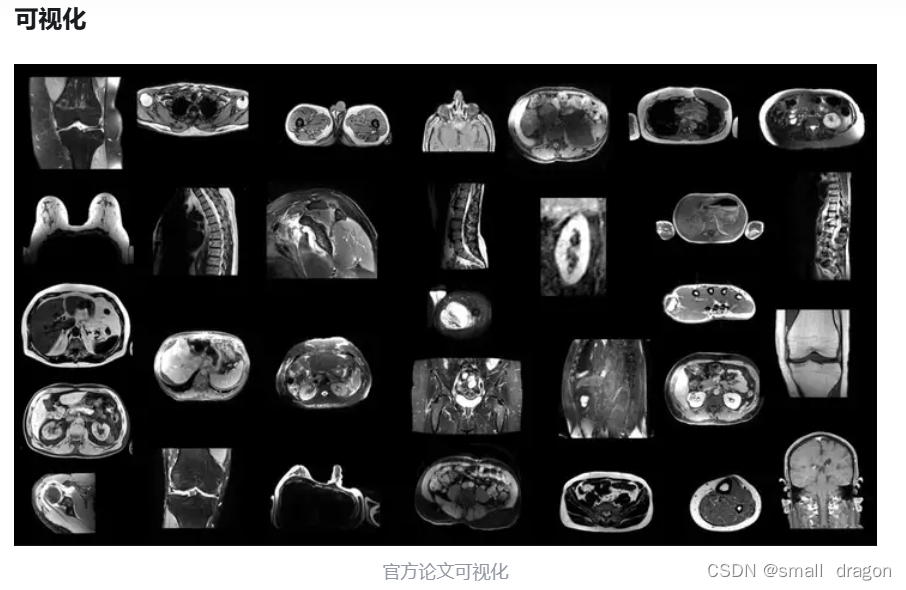

2、TotalSegmentator MRI

数据集包含了 298 例 MR 图像,并提供多达 56 种不同常用解剖结构的分割标注。其中,251 例 MR 图像来自 2011 年至 2023 年间巴塞尔大学医院的图像存档和通信系统(PACS),另外 47 例 MR 图像来自影像数据共享平台(Imaging Data Commons,IDC),以增加图像的多样性。该数据集源自日常临床工作中的随机抽样,代表了一个可推广到临床应用的真实世界数据集。它涵盖了各种不同的病变、扫描仪、成像序列和来自不同医疗机构的数据。值得注意的是,尽管官方论文提到包含 59 种类别,但公开的数据集中仅提供 56 类标注,略有差异。

磁共振成像(MRI)能够在不使用电离辐射的情况下提供人体详细解剖图像,对于神经系统疾病、肌肉骨骼损伤等多种临床诊断至关重要。尽管 TotalSegmetator (CT) 数据集已被广泛使用,但 MRI 图像分割仍面临挑战,主要是由于不同序列和身体部位的成像参数和协议变化,影响算法的普遍性和准确性。TotalSegmentator MRI 数据集扩展了处理各种 MRI 图像的能力,旨在开发一个开源且易用的分割模型,能够自动且稳健地分割主要解剖结构,而不依赖于具体的 MR 序列。